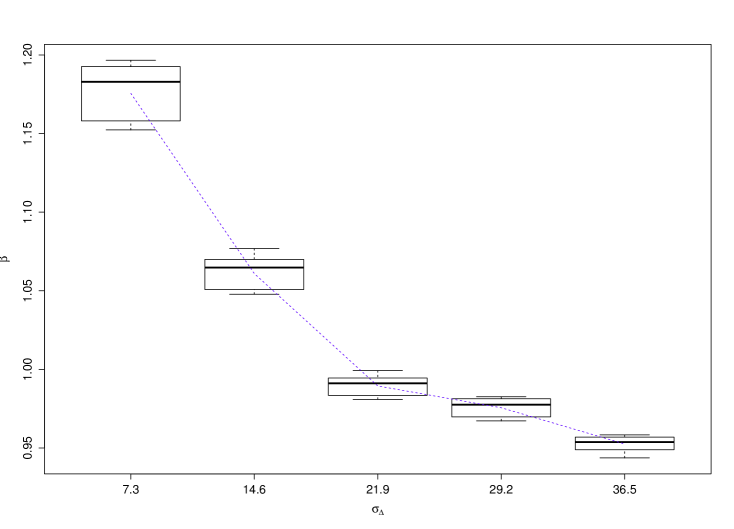

The posterior estimate of the inverse temperature was almost identical for all 27 cone-beam CT scans. Without the external field prior, the pooled 95% HPD interval for was . With the prior, the HPD interval for converged to . As discussed in Section 4.3, the value of changes with the strength of the prior, as measured by the standard deviation.

The value of the inverse temperature obtained by path sampling also changed as the uncertainty in the prior increased. Fig. 5 shows the posterior mean of for the 27 cone-beam CT scans. It is evident from Eq. (4) that is a free parameter that balances the strength of spatial association against the external field (which in our model is data prior). The external field prior becomes weaker as the standard deviation increases, thus the value of is lower to compensate.